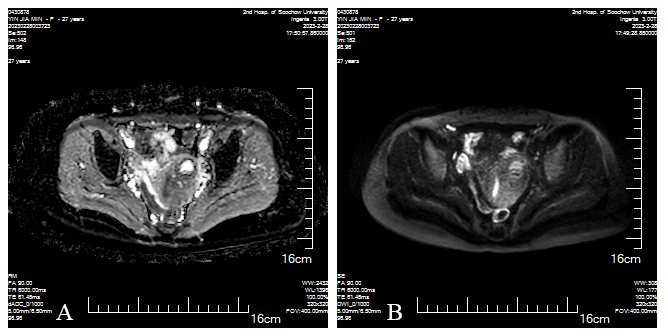

Fig. 4.

March 2, dADC (D-1), DWI (D-2) showed low signal intensity on the left side of the uterus. (A) dADC and (B) DWI both confirm low signal intensity on the left side of the uterus, with fluid present within this lesion, a possibility of gestational sac rupture and bleeding is suggested.